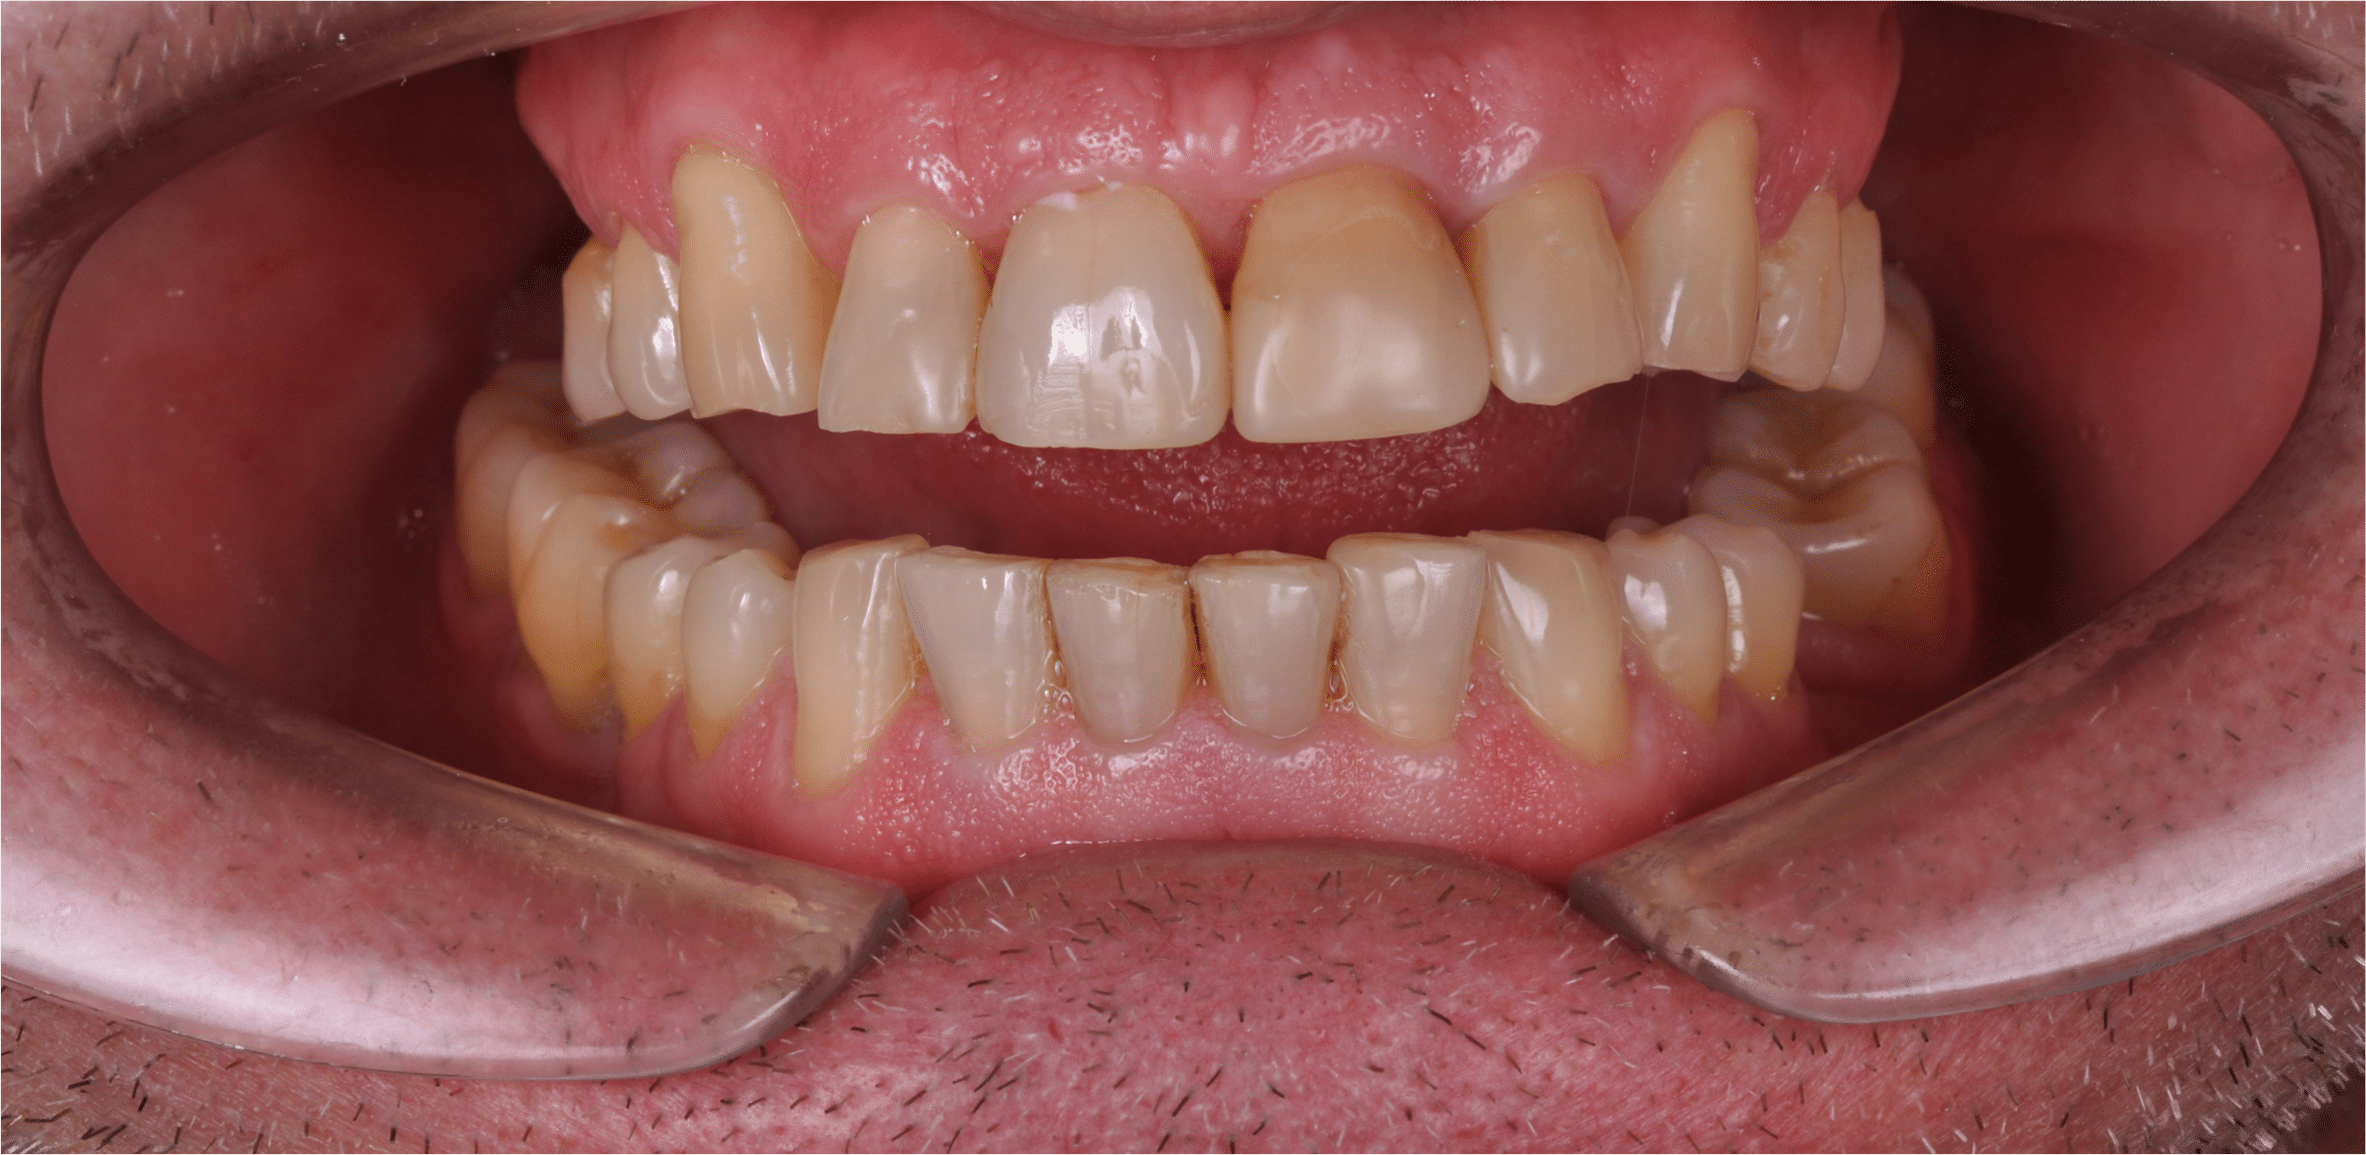

Doar astfel putem crea profilul de emergență corect al coroanei dentare, ceea ce permite conformarea papilei și a sulcusului.